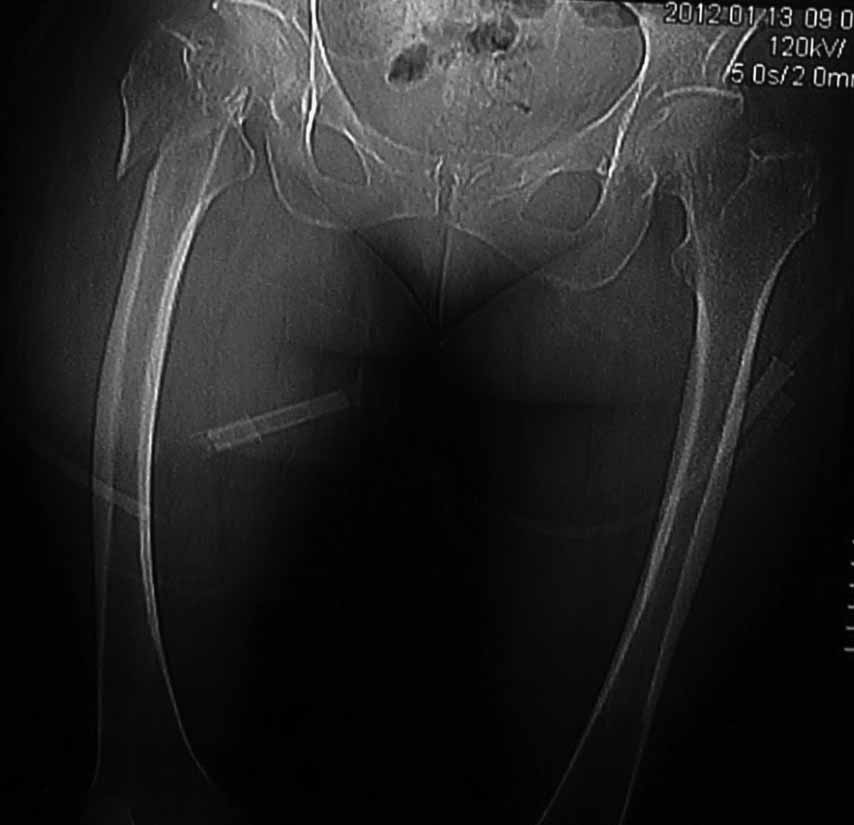

Пациентка 53 лет. ДТП 09.01.12: сочетанная травма: перелом 2-5 ребер справа, ушиб легких;

перелом обеих лонных костей без смещения; закрытый перелом проксимального конца правой

бедренной кости; открытый оскольчатый внутрисуставной перелом проксимальных концов

костей правой голени.

Бедро одномоментно делать не стал, не было уверенности в наличии перелома на уровне шейки. Во время операции смотрел тазобедренный сустав под ЭОПом,

головка неподвижна. После операции повторили КТ, стало очевидно, что имеется субкапитальный перелом. Что делать, остесинтез или протезирование? Если остеосинтез, то чем? Заранее благодарен за советы.